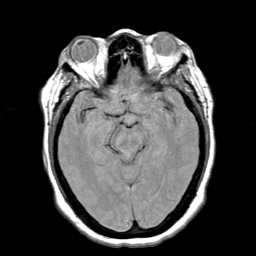

Cerebral hemorrhage, MR Study mr-pd -- Slice #10

[Home][Help][Clinical] Slice 10